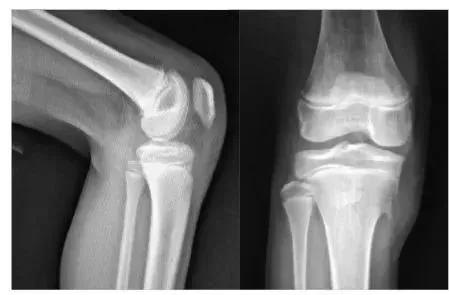

一、X线

1.早期表现为局部软组织肿胀,髌韧带增粗肥厚显著,继之则产生肌腱的钙化和骨化,胫骨结节呈舌状隆突,密度增高、碎裂,且与骨干轻度分离,形成大小、形态不一的骨碎块。

2.分离部位的骨骺边缘可见小的裂隙状缺损。

3.骨骺修复后胫骨结节可恢复正常或略有增高隆起,但常可留下分离的碎骨块,至成年时为胫骨结节上方的游离体,长期游离于髌韧带内。

男,11岁,胫骨前结节稍肿胀,右膝疼痛两月余,按压疼痛,胫骨结节下部与骨干分离。

X线片可显示胫骨结节骨软骨炎患者骨质及软组织的异常改变,是诊断胫骨结节骨软骨炎颇有价值的方法,对一些早期及可疑患者可进一步做CT或MRI检査。